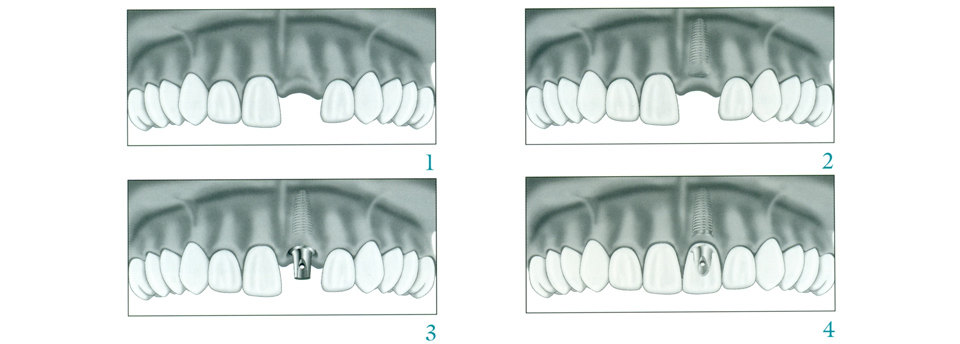

Missing teeth can be a nuisance, both cosmetically and functionally; you may feel self-conscious about a gap in your smile, and that gap will almost certainly cause problems with biting and chewing. While there are several procedures dentists use to fill in gaps left by missing teeth, dental implants are by far the most natural-seeming in form and function. A dental implant is nearly indistinguishable from a natural tooth and can last a lifetime with proper maintenance. Click here to find out more.